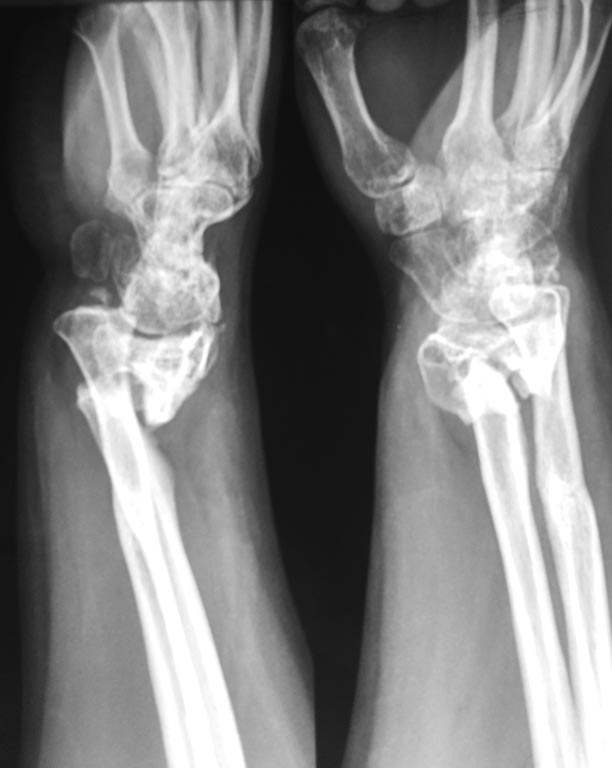

Спасибо за помощь. Результаты оперативного лечения.